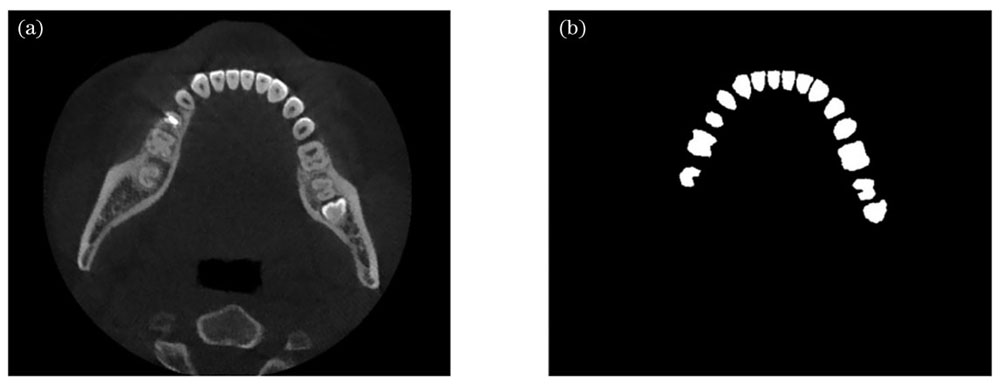

同时本文算法有较强的抗干扰能力。采用患者牙齿含有填充物的图像进行测试,效果如

图 8. 带有牙齿填充物的图像识别效果。(a)待识别图像;(b)改进U-net方法识别效果

Fig. 8. Recognition result of image with dental fillings. (a) Image to be recognized; (b) recognition result using improved U-net model